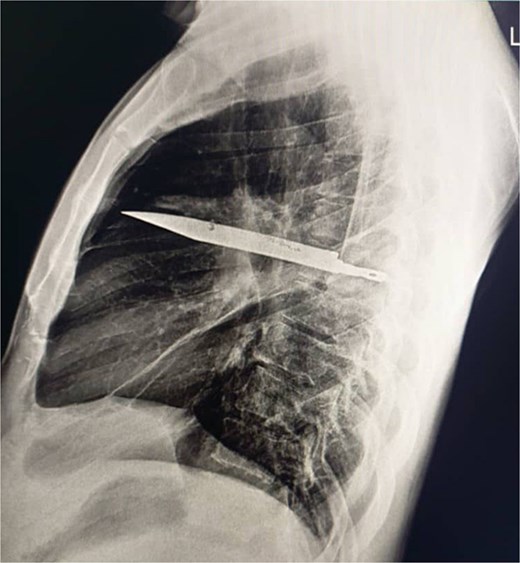

Initial imaging with a lateral chest radiograph demonstrated a retained metallic object in the mid-thorax, with surrounding opacification likely representing a resolving or chronic loculated hematoma or post-traumatic fibrosis, a sequela of the patient's stab wound (Fig. 2). Subsequent computed tomography (CT) imaging (Fig. 3a and b) revealed a retained foreign metallic object traversing the right chest. The entry point was identified through the right scapula, between the 5th and 6th posterior intercostal spaces, with the tip extending to the 3rd and 4th anterior intercostal spaces. CT also demonstrated healed fractures of the right scapula, 5th and 6th ribs posteriorly, and the 3rd rib anteriorly. An elliptical area of consolidation with central hypodensity was observed, further supporting the interpretation of a resolved or chronic loculated hematoma. The remainder of the lung parenchyma appeared unremarkable.

Lateral chest radiograph demonstrating a retained metallic object (knife) in the mid-thorax with surrounding opacification consistent with post-traumatic fibrosis following a stab wound.